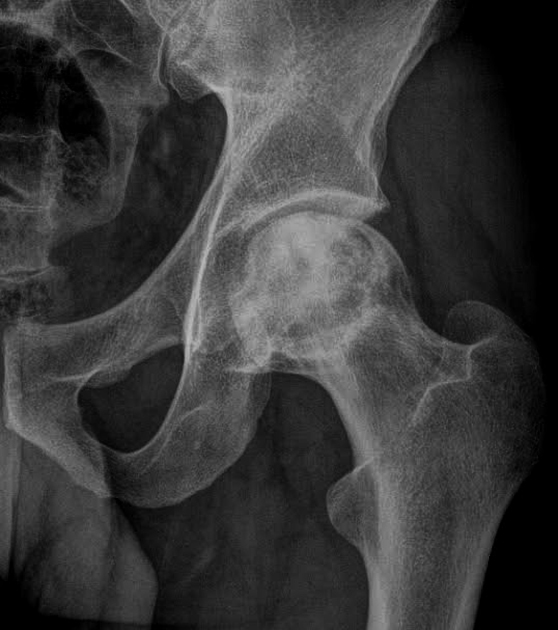

Results from the loss of blood supply - the femoral head is the most frequent site of it - often necessary to obtain two radiographs in patients with this condition. The first is taken with normal density, whereas the second is made with increased kVp to allow for adequate penetration of the more opaque ischemic bone.

Ischemic Necrosis

Associated with ischemic necrosis of bone. Ischemia results from poor blood supply to the bone. Affects the epiphyses and may be mistaken for tuberculosis of the skeletal system. Tends to occur in males between the ages of 5 to 10 years and often follows injury to the affected hip. Radiographically the bone in the center of the epiphysis is fragmented and the head of the femur is flattened.

Legg-Perthes Disease